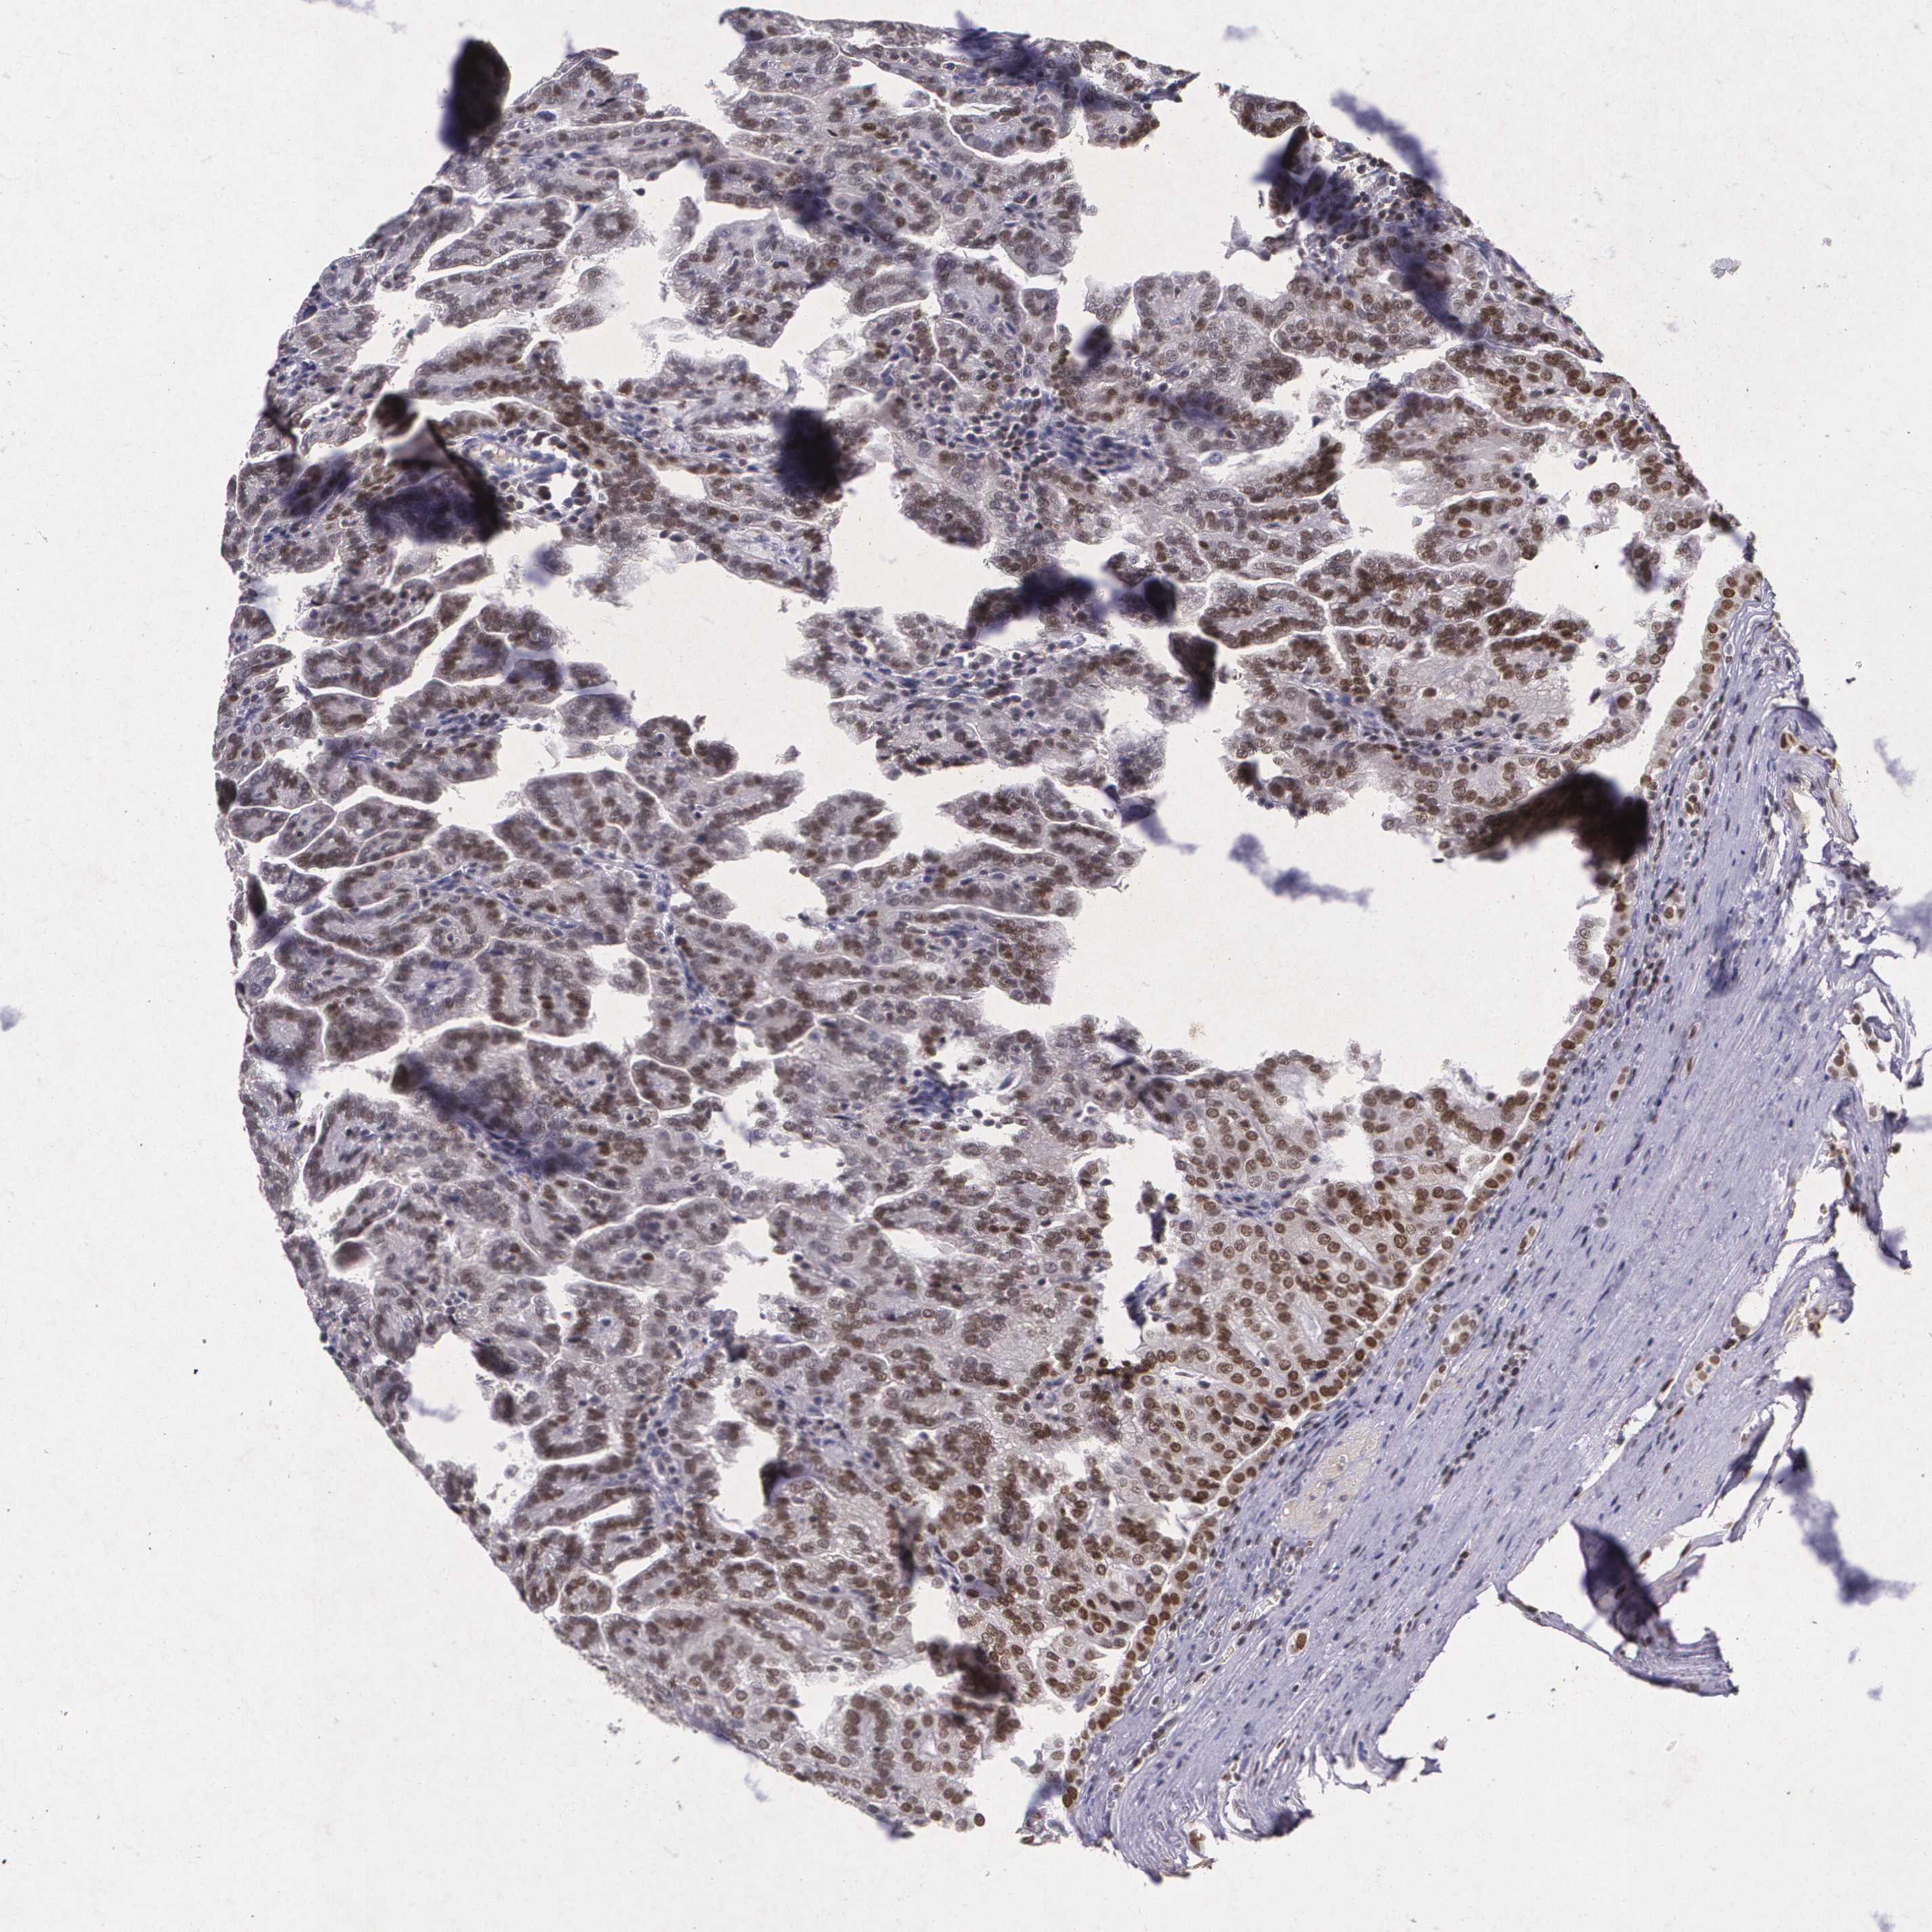

KIDNEY RENAL CLEAR CELL CARCINOMA (VALIDATION) - Interactive survival scatter ploti

The Survival Scatter plot shows the clinical status (i.e. dead or alive) for all individuals in the patient cohort, based on the same data that underlies the corresponding Kaplan-Meier plots. Patients that are alive at last time for follow-up are shown in blue and patients who have died during the study are shown in red.

The x-axis shows the expression levels (FPKM) of the investigated gene in the tumor tissue at the time of diagnosis. The y-axis shows the follow-up time after diagnosis (years). Both axes are complimented with kernel density curves demonstrating the data density over the axes. The top density plot shows the expression levels (FPKM) distribution among dead (red) and alive patients (blue). The right density plot shows the data density of the survived years of dead patients with high and low expression levels respectively, stratified using the cutoff indicated by the vertical dashed line through the Survival Scatter plot. This cutoff is automatically defined based on the FPKM cutoff that minimizes the p-score. The cutoff can be changed by dragging the vertical line or by entering a cutoff value in the square labeled "Current cut-off".

Under the Survival Scatter plot the p-score landscape (black curve; left axis) is shown together with dead median separation (red curve; right axis). Dead median separation is the difference in median mRNA expression between patients who have died with high and low expression, respectively. It is calculated as follows: median FPKM expression of dead patients with high expression - median FPKM expression of dead patients with low expression. This is intended to aid the user in visually exploring custom cutoffs and the associated p-scores and dead median separation.

Individual patient data is displayed and can be filtered by clicking on one or more of the category buttons on the top of the page. Categories describing expression level and patient information include: high, low, alive, dead, female, male and tumor stages. The scale of the x-axis can be toggled between linear and log-scale by clicking on the "x log" button. Mouse-over function shows TCGA ID, patient information and mRNA expression (FPKM) for each patient.

& Survival analysisi

Kaplan-Meier plots summarize results from analysis of correlation between mRNA expression level and patient survival. Patients were divided based on level of expression into one of the two groups "low" (under cut off) or "high" (over cut off). X-axis shows time for survival (years) and y-axis shows the probability of survival, where 1.0 corresponds to 100 percent.

MGMT is not prognostic in Kidney Renal Clear Cell Carcinoma (validation)

Best expression cut offi

Based on the FPKM value of each gene, patients were classified into two groups and association between prognosis (survival) and gene expression (FPKM) was examined. The best expression cut-off refers the FPKM value that yields maximal difference with regard to survival between the two groups at the lowest log-rank P-value. Best expression cut-off was selected based on survival analysis .

When clicking on this number, the vertical dashed line indicating cut-off, the interactive survival plot, and the Kaplan-Meier curve will be adjusted to show results based on the best expression cut-off.

: 32.9

TCGA RNA samplesi

RNA-seq data is reported as average FPKM (number Fragments Per Kilobase of exon per Million reads), generated by the The Cancer Genome Atlas (TCGA) .

Normal distribution across the dataset is visualized with box plots, shown as median and 25th and 75th percentiles. Points are displayed as outliers if they are above or below 1.5 times the interquartile range. FPKM values of the individual samples are presented next to the box plot.

Average pTPM 35.7

Number of samples 100